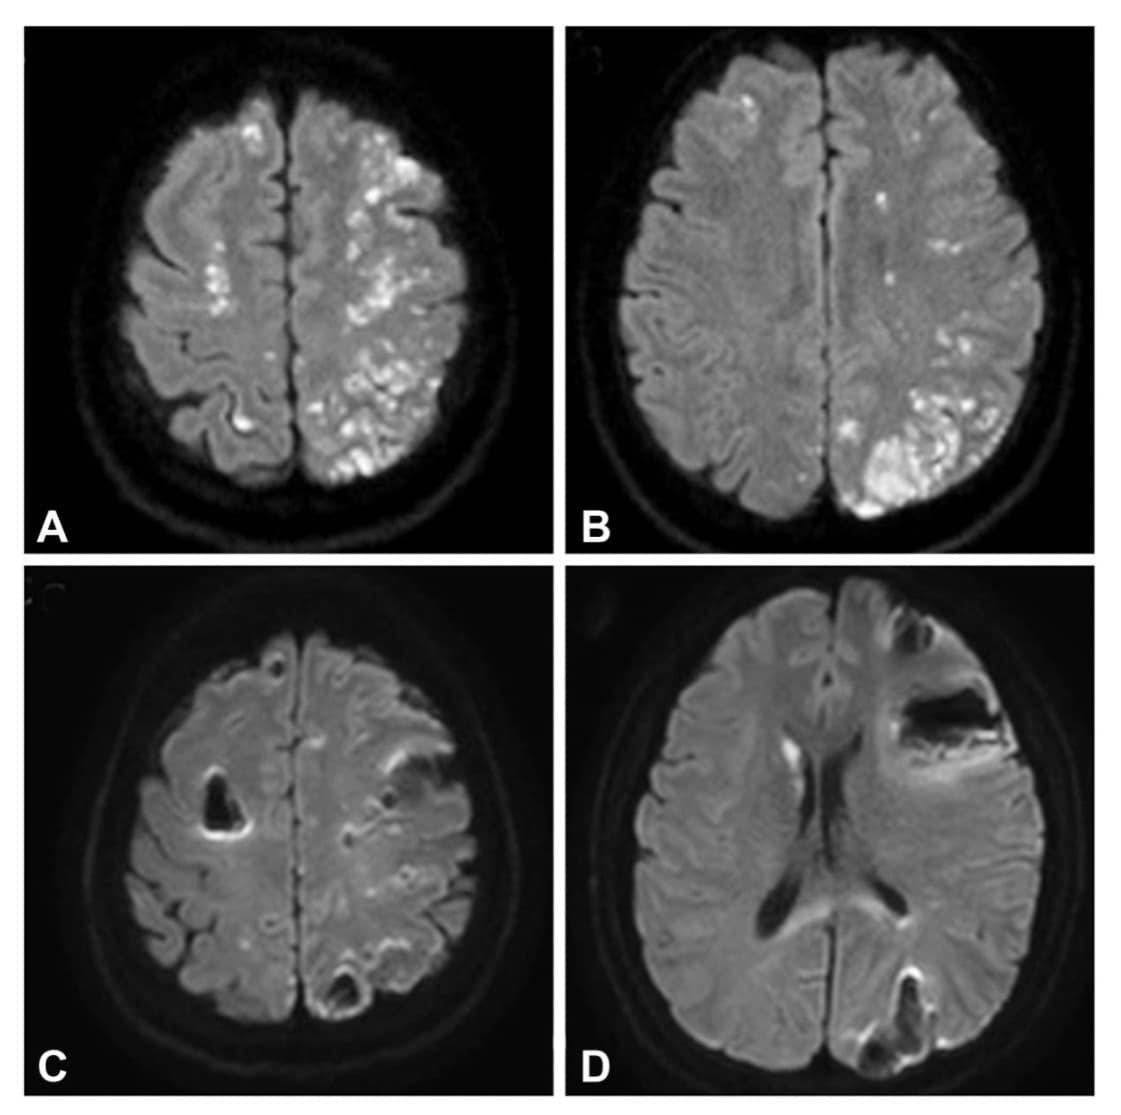

วันที่ 6 ก.ค. 65 เพจเฟซบุ๊ก Ramadermatology โพสต์ข้อความเตือนภัยถึงการฉีดฟิลเลอร์ ระบุว่า ขอนำเสนอเคสที่น่าสนใจเกี่ยวกับผลข้างเคียงจากการฉีด HA filler เคสผู้ป่วยหญิงอายุ 39 ปี ได้รับการฉีด HA filler บริเวณ glabella (แสกหน้า) บริเวณระหว่างคิ้ว และเหนือจมูก ส่วนนี้จะเป็นสันนูนเล็กน้อยเชื่อมระหว่างสันคิ้ว ภายหลังฉีดมีอาการตามัว ปวดตาข้างซ้าย ซึมลง ร่วมกับมีอาการขาอ่อนแรงทันที

ในผู้ป่วยรายนี้ ได้รับการรักษาด้วย methylprednisolone ฉีด อย่างไรก็ตามในเคสนี้ไม่ได้ทำการฉีดสลายด้วย hyaluronidase ติดตามภายหลังการรักษา 2 สัปดาห์ พบว่าอาการอ่อนแรงเริ่มดีขึ้น แต่ผู้ป่วยยังมองไม่เห็นเหมือนเดิม